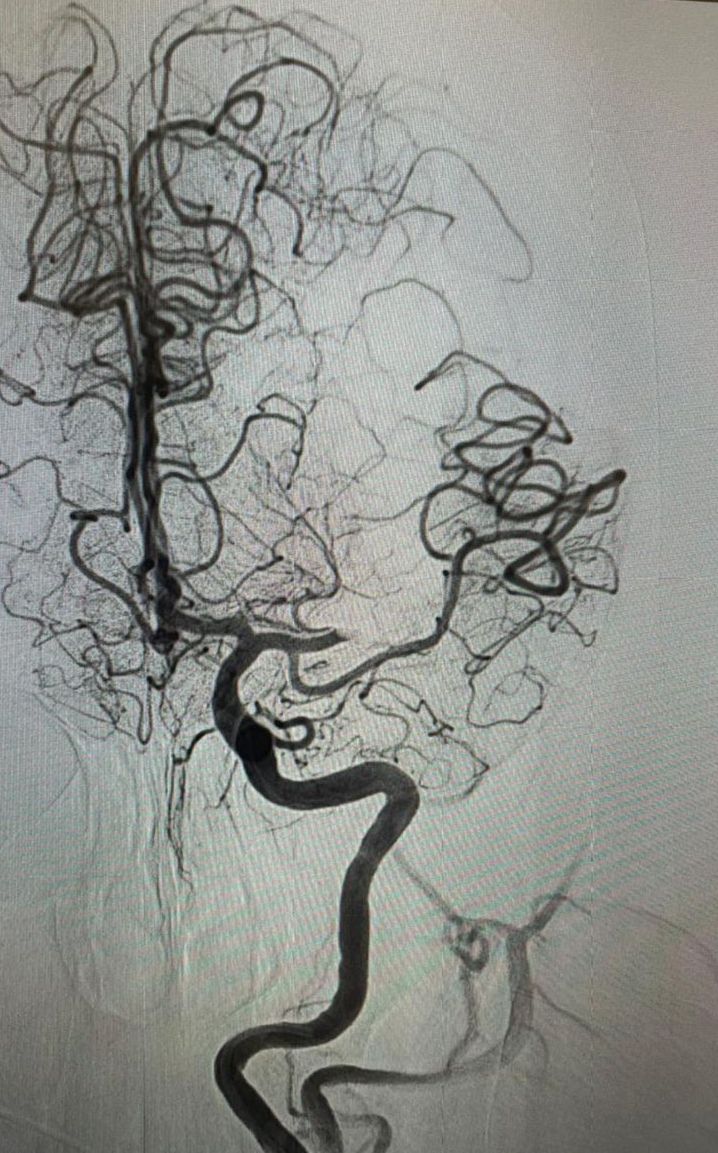

Pensiones Civiles del Estado (PCE) realiza cirugía de rescate cerebral vascular a derechohabiente femenina de 72 años de edad que presentó una embolia cerebral.

La cirugía fue realizada por el médico especialista de Pensiones Civiles, Alejandro Rodríguez Orozco, radiólogo neuro intervencionista, junto con el equipo de hemodinamia del Hospital Ángeles Chihuahua.

La paciente con antecedente de arterioesclerosis y lesiones en las carótidas, perdió la fuerza de forma súbita en la mitad de su cuerpo, afasia, pérdida del lenguaje y parálisis facial, por ello, se le realizó una resonancia magnética, en la que se detectó la obstrucción de una arteria por un coágulo, identificando la zona afectada y se hizo el rescate, que consiste en introducir catéteres desde la ingle hasta el cerebro.

Con este procedimiento, la derechohabiente, ha recuperado la circulación sanguínea hacia el cerebro, el lenguaje y el movimiento se irá recuperando paulatinamente conforme se progrese con las sesiones de fisiatría, tratamiento farmacológico y cambios en el estilo de vida.